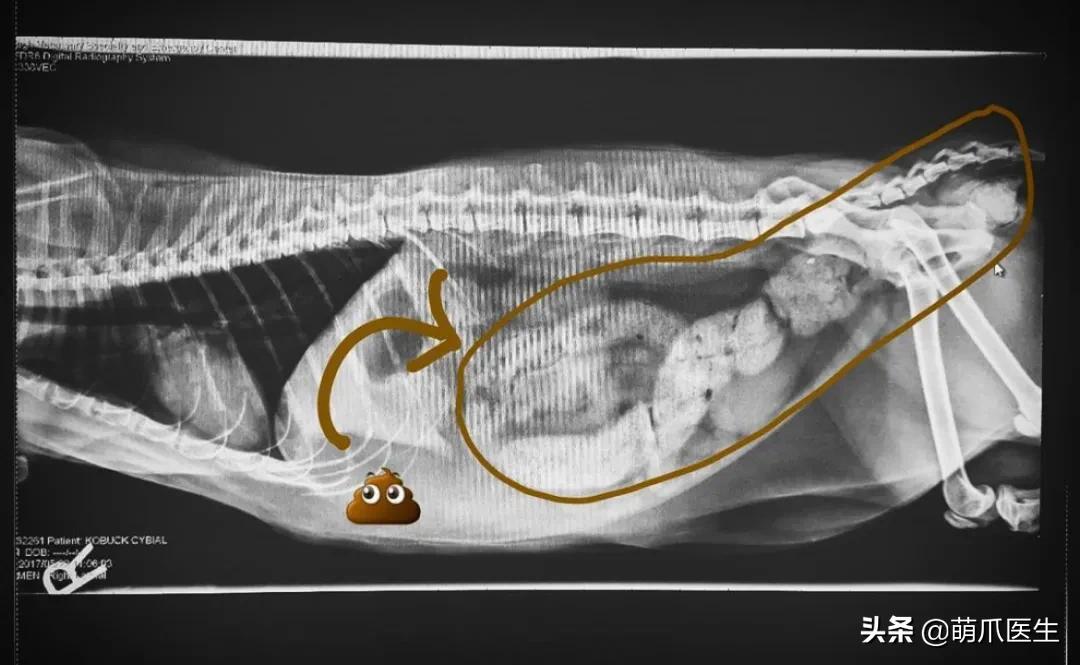

带怀孕的猫妈妈去做检查,X光能拍出它 怀了几个宝宝、宝宝们的脊椎是否正常。

当然,你也可能在拍片后收获一肚子的猫屎!